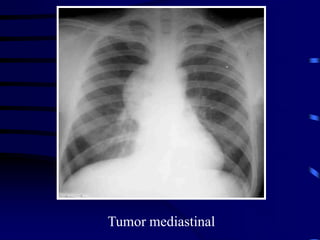

Tumor mediastinal anterior

Focalización del caso anterior

Tumor mediastinal